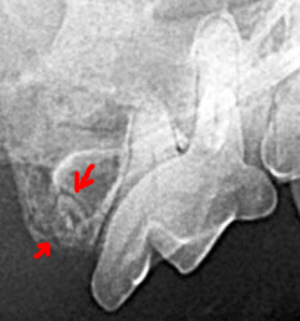

Here are a couple of recent patients that had problems we’d have missed without x-rays. On the left, the dark halo around the root signifies an abscess in a chihuahua. On the right is a root fragment in a Birman cat – the gingiva had grown over, making it invisible without x-rays.